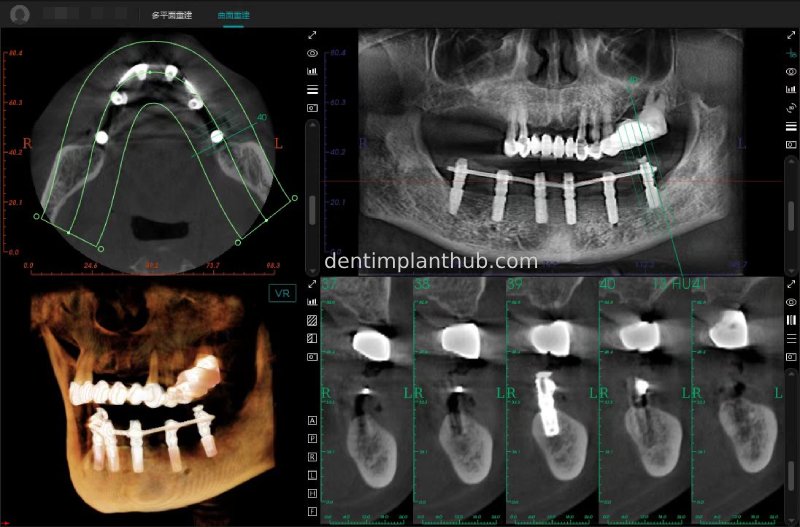

Maxillary condition as shown by CBCT on 13/5/24

16

14

12

22

24

26

Details of implant sites, protocols, implant types, composite abutments, 13.5.24

16, implant model 4810, requires an internal elevation of the maxillary sinus floor and an RC series straight composite abutment;

14, implant model 4812, requires an RC series 15° composite abutment;

12, implant model 4112, requires an RC series 30° composite abutment;

22, implant model 4112, requires an RC series 30° composite abutment;

24, implant model 4812, requiring an RC Series 15° composite abutment;

26, implant model 4810, requiring an internal maxillary sinus floor lift, requiring an RC Series straight composite abutment;